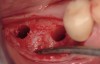

The patient was a 71-year-old man with significant caries and subsequent bone loss associated with tooth No. 30. The septal bone was lost, with the exception of the coronal aspect, resulting in a "bridge of bone" connecting the buccal and lingual cortices of the site (Figure 1). After reflection of the full-thickness buccal and lingual flaps, extraction, and manual and ultrasonic debridement of the socket to remove all visible soft-tissue remnants, the defect was obturated with the rhBMP-2/ACS material (Figure 2).

Figure 1  Extraction and debridement of tooth No. 30.

Figure 1